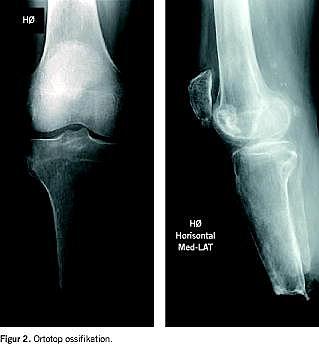

II. En 71-årig mand, der havde udtalt aterosklerotisk sygdom, hypertension og type 2-diabetes, tidligere akut myokardieinfarkt og aortaaneurisme, blev i 2003 crusamputeret efter arteriel emboli i højre a. poplitea. Det postoperative forløb var ukompliceret uden smerter og med god vægtbæring på stumpdelen. Få måneder efter amputationen fik patienten tryksår ved stumpspidsen. Området var velvaskulariseret med god behåring, men med palpabel knogle umiddelbart under huden. Dette blev bekræftet ved en røntgenkontrol (Figur 2 venstre foto). En spids, skarp eksostose med ovenliggende bursa ved det laterale hjørne excideredes. Ni måneder senere var patienten fortsat smertefri.

III. En 74-årig kvinde fik efter total hoftealloplastik arteriel emboli og deraf følgende crusamputation. Efter næsten tre år, hvor hun havde været mobiliseret med protese, fik hun et inficeret sår ud for stumpspidsen. Dette blev af flere omgange på baggrund af dyrkningssvar behandlet med antibiotika hos egen læge, men uden heling. Der var god gennemblødning, og radiologisk fandt man tegn på ossifikation (Figur 2 højre foto), som blev fjernet kirurgisk. Såret helede, og patienten kunne mobiliseres uden gener fra sin protese.